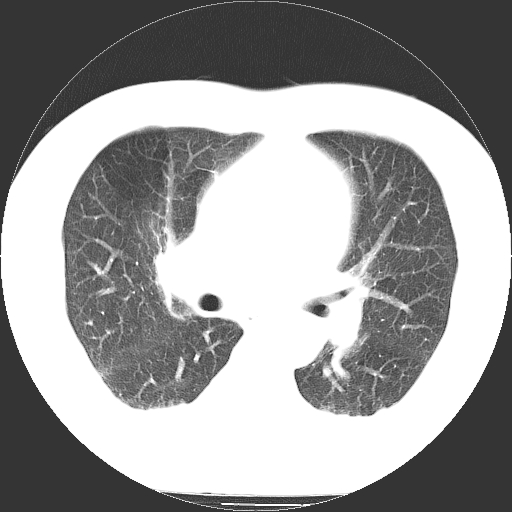

男,65岁,咳嗽、咳痰、发热5天。

慢支 肺间质纤维化合并感染!

支气管扩张合并感染,胸膜肥厚

考虑慢支并感染,肺间质纤维化。

两肺间质性炎症并感染

慢支,肺心病

支持慢性支气管炎伴感染,双侧少量胸腔积液.

两肺间质纤维化,支扩合并感染,双侧胸腔积液

感染,肺间质纤维化。

慢支 肺间质纤维化合并感染

支持慢性支气管、肺间质纤维化合并感染。

慢性支气管炎并感染,支扩,双侧少量胸腔积液.